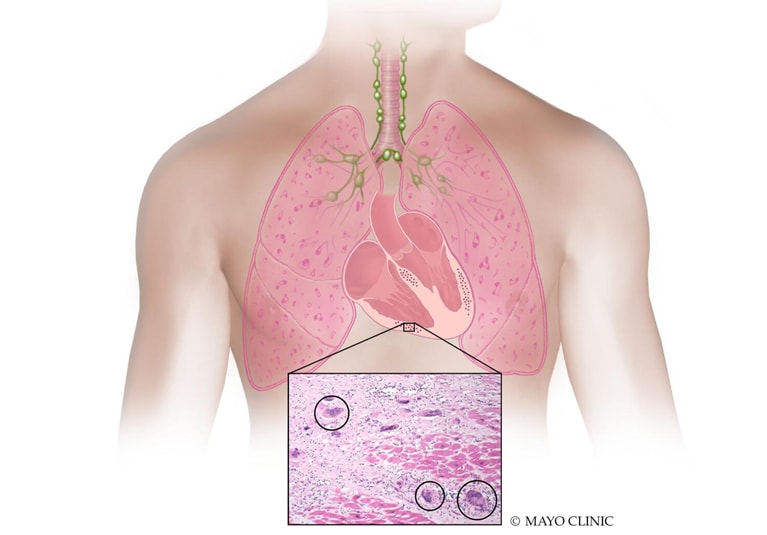

Cardiac sarcoidosis global experts reach consensus on optimal imaging for patients

A JACC: Cardiovascular Imaging study shows how international cardiac sarcoidosis experts worked together to help determine when to use advanced imaging for patients with the rare autoimmune disorder.